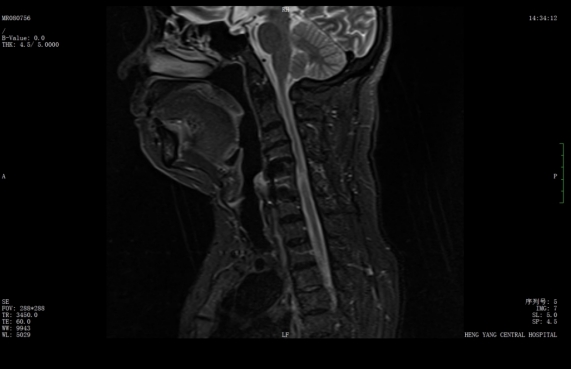

該患者此前因膽囊結(jié)石祁東縣人民醫(yī)院治療,來自衡陽市中心醫(yī)院駐該院副院長(zhǎng)李攀峰為其主刀進(jìn)行手術(shù),術(shù)后患者恢復(fù)良好。后因突發(fā)四肢癱瘓、生活無法自理,為尋求進(jìn)一步治療,經(jīng)醫(yī)聯(lián)體通道轉(zhuǎn)入衡陽市中心醫(yī)院。脊柱外科錢軍博士團(tuán)隊(duì)接診后,迅速組織詳細(xì)問診、體格檢查及系統(tǒng)術(shù)前評(píng)估。查體顯示患者四肢關(guān)鍵肌肌力僅I級(jí),感覺功能明顯減退,結(jié)合影像學(xué)結(jié)果,診斷為頸脊髓損傷伴不全癱,有明確手術(shù)指征。

考慮到患者20年前曾有頸脊髓外傷史,并于外院行頸椎前路手術(shù),此次手術(shù)區(qū)域存在嚴(yán)重瘢痕粘連,極大增加了手術(shù)難度與風(fēng)險(xiǎn)。錢軍博士團(tuán)隊(duì)迅速啟動(dòng)多學(xué)科會(huì)診,為患者制定個(gè)性化手術(shù)方案,最終決定施行頸椎后路手術(shù),擴(kuò)大椎管容積,徹底解除神經(jīng)壓迫問題。

wps1.jpg

術(shù)前核磁共振提示:頸椎椎管狹窄、頸脊髓信號(hào)改變